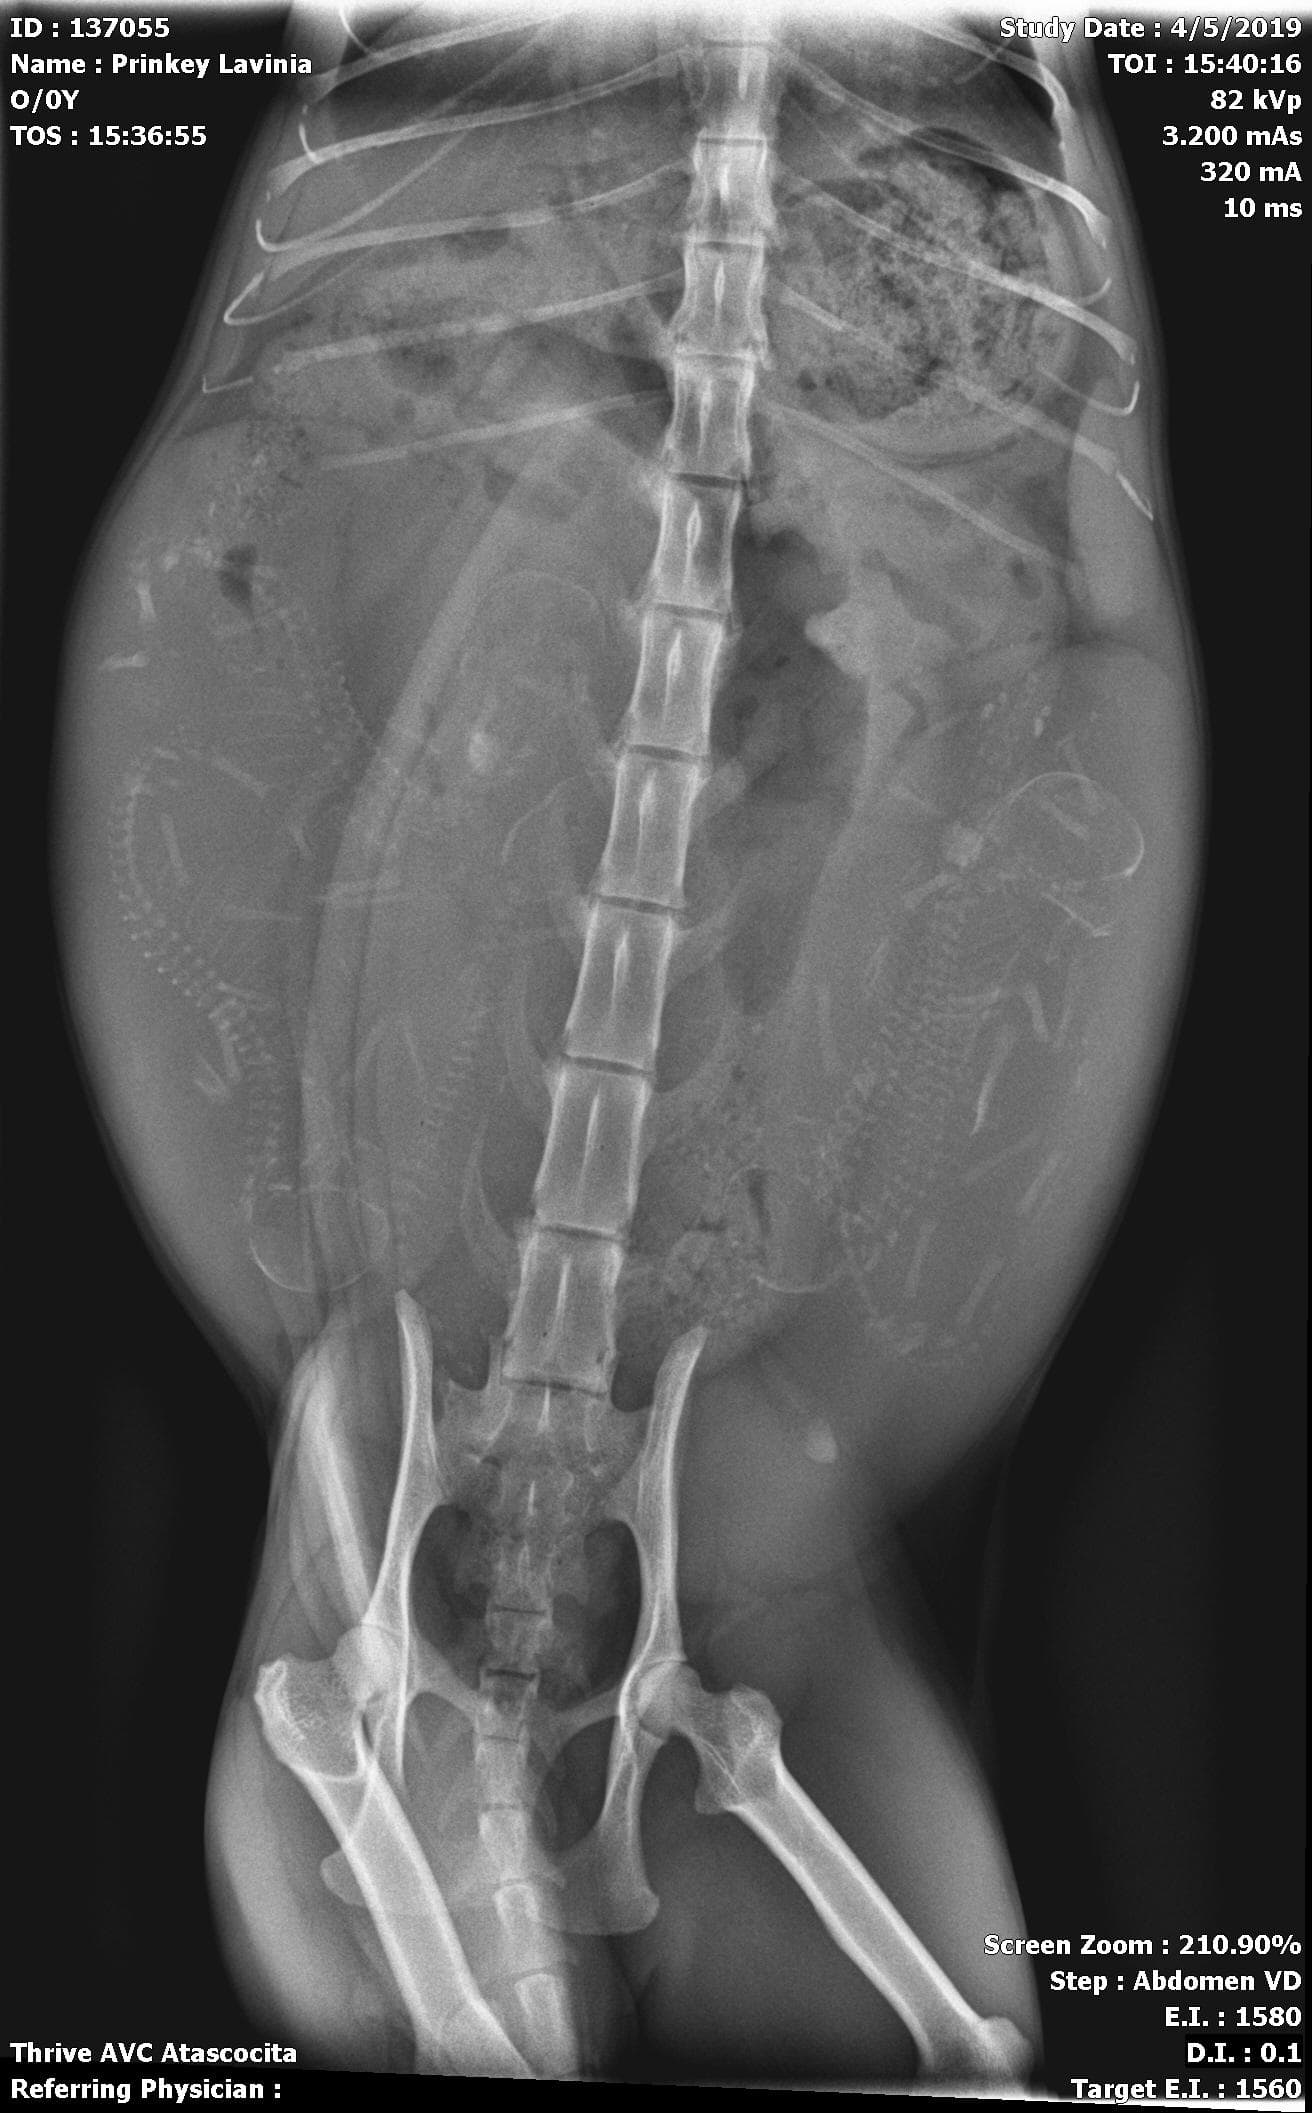

My Sphynx gave birth to 5 healthy babies Monday morning (and some late Sunday night) The X-ray showed 5 possibly 6 babies. I felt like i felt and saw another still in there but she hasn’t pushed since she birthed the last one. She’s eating and drinking fine Acting completely normal. My er vet said to come in if she acts unusual but I’m worried that she won’t pass the last one And would an oxytocin injection possibly fix the problem? I heard about interrupted labor so maybe it’s that?

I recommend you call your vet and have Lavinia examined to make sure all is well. They may recommend another x-ray just to make sure there are no complications and no kittens left in the birth canal.